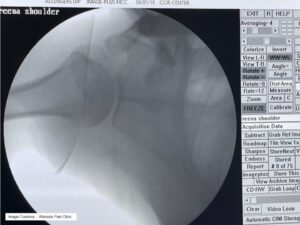

Hydrodilatation (Distension Arthrogram)

- Procedure : Hydrodilatation is a minimally invasive procedure that entails the injection of a sterile fluid (typically saline) into the joint capsule, stretching it and breaking up adhesions.

- Mechanism : The injected fluid distends the capsule, physically separating adhesions and promoting the release of fibrotic tissue. This procedure also helps to restore joint lubrication and improve range of motion.